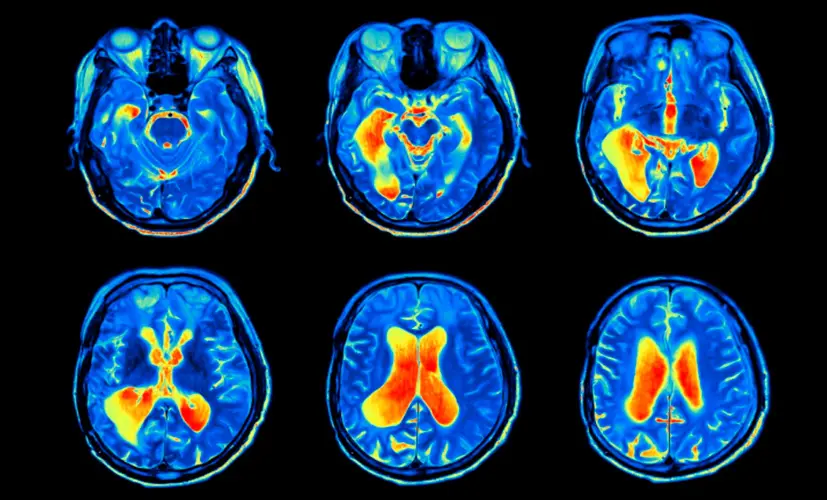

– The blood vessels throughout the body are closely connected. If the vessels in the brain are clogged with plaque, they receive fewer nutrients. That's where cognitive decline and other serious issues begin.

The same goes for the heart. People with cognitive decline are 59% more likely to develop coronary artery disease or atherosclerosis, and 34% more likely to suffer a stroke. As we've discussed, cognitive decline can also lead to depression, which further increases the risk of cardiovascular disease. Add in the overuse of Aricept, which negatively impacts brain function-and suddenly, the person suffering from cognitive decline is almost guaranteed to face fatal neurological complications.